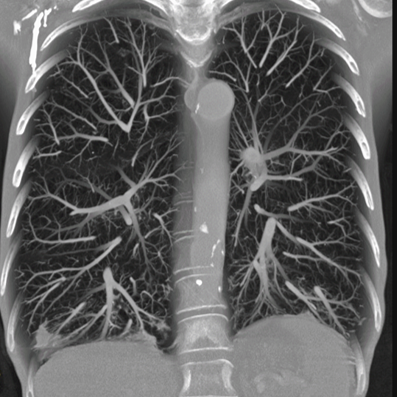

• the computed tomography system 64-slice manufactured by NIPK Electron Co. for primary assessment and differential diagnostics of chest diseases, as well as for revealing concomitant diseases. The modular CT unit can be equipped with a computed tomography system with another slice number as an option. According to the interim methodological guidelines “Prevention, Diagnostics, and Treatment of a new Coronavirus Infection” developed by the Ministry of Health of Russia, a CT scan is considered one of the basic methods of COVID-19 diagnosis.

The computed tomography system 64-slice (CT) installed in the module unit is equipped with a wide set of specialized software applications for diagnostic imaging in patients with respiratory disorders, vascular abnormalities, cancer, as well as for assessment of cerebral, renal, and hepatic blood supply. Thanks to this, CT is in high demand not only during the COVID-19 pandemic.